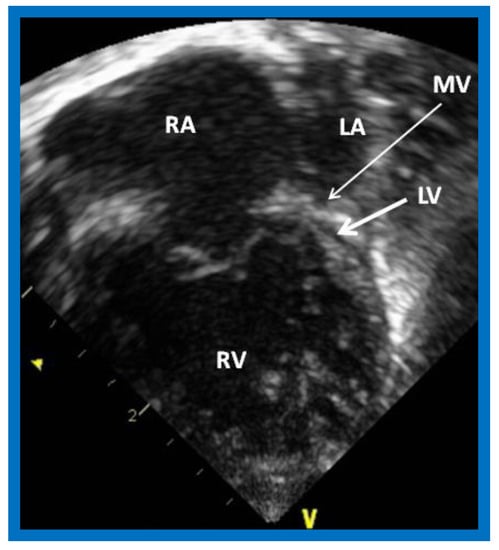

The phrase “HLHS” was first suggested by Noonan and Nadas [2] to characterize a very small left ventricle with poorly developed aortic and mitral valves. The left ventricle (LV) is usually a slit-like cavity (Figure 1) with thick muscle, especially when mitral atresia co-exists. The aortic valve is atretic or markedly narrowed with annular hypoplasia. Similarly, the mitral valve is markedly stenotic, hypoplastic or atretic (Figure 1). The LV is very small when the mitral valve is open. Endocardial fibroelastosis is often present. Hypoplasia of the ascending aorta is present, and its diameter is usually 2–3 mm (Figure 2). However, it is adequate to supply ample coronary blood flow retrogradely. The left atrium is very small (Figure 1). The interatrial septum is usually thickened with a small patent foramen ovale (PFO) and rarely the atrial septum is intact. A patent ductus arteriosus (PDA) is classically present and is necessary for the baby to survive [3,4,5].

Figure 1.

Echocardiogram in an apical 4-chamber view of a baby with hypoplastic left heart syndrome, showing a strikingly small, slit-like (thick arrow) left ventricle (LV), obviously enlarged and hypertrophied right ventricle (RV), and a dilated right atrium (RA). The atretic mitral valve (MV) (thin arrow) and hypoplastic left atrium (LA) are also seen.